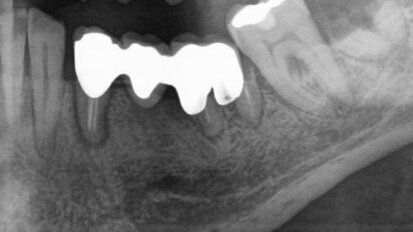

Rehabilitace Straumann